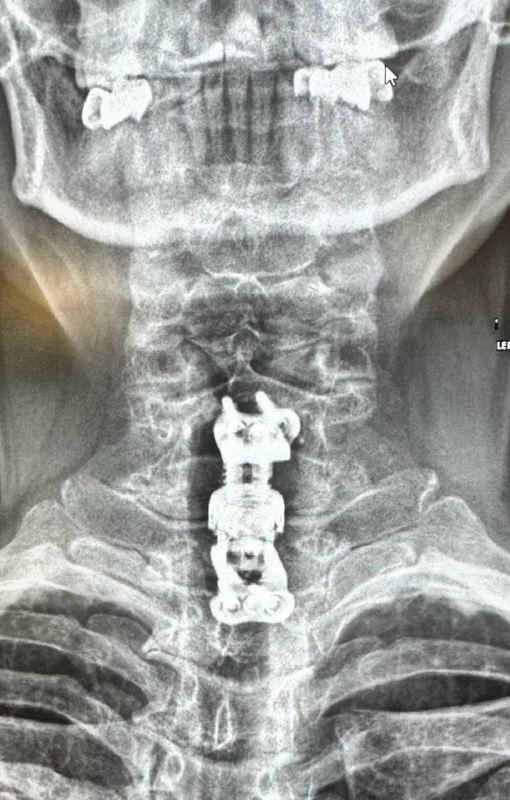

Во время дообследования врачи выявили патологический перелом тел шестого и седьмого позвонков из-за спондилодисцита. Медики решили прооперировать женщину и устранить компрессию спинного мозга, удалить тела поражённых позвонков и стабилизировать позвоночный столб.

Также в ходе операции врачи установили телоскопический телозамещающий имплант, чтобы обеспечить стабильность в позвоночно-двигательных сегментах. Такую операцию в регионе выполнили впервые.